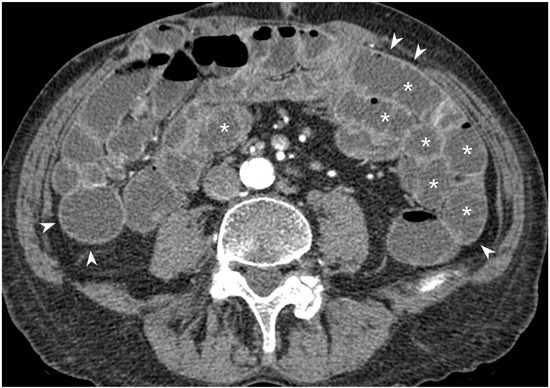

5.1. Active Subtype